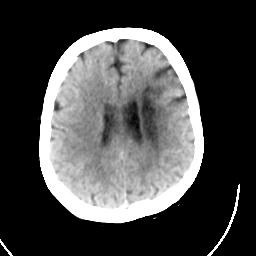

CT Study #1 -- Slice #17